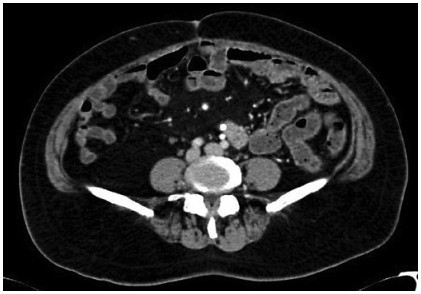

Abstract: Mixed neuroendocrine nonneuroendocrine neoplasms (MiNENs) are rare neoplasms of the gastrointestinal tract, where the neuroendocrine as well as the nonneuroendocrine components each comprise at least 30% of the tumor. Of all cases of colorectal malignancies, MiNENs constitute around 3–9.6%, with only a few cases reported to be arising in the cecum. Since majority present with nonspecific clinical and radiological findings, its diagnosis preoperatively is almost impossible and these are usually diagnosed after histopathological examination of the resected specimen. Owing to the rarity of these tumors as well as lack of complete molecular characterization, optimal treatment remains unestablished. We, here, report a rare case of MiNENs of the cecum infiltrating the right psoas muscle and presenting with perforation for which right hemicolectomy and en bloc excision of the involved psoas muscle was done followed by adjuvant chemotherapy.